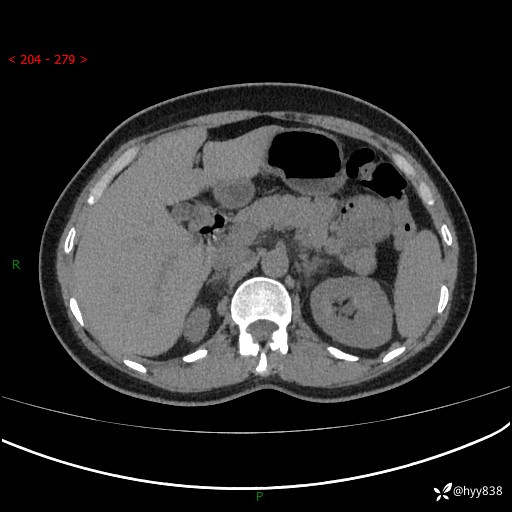

上腹部CT平扫